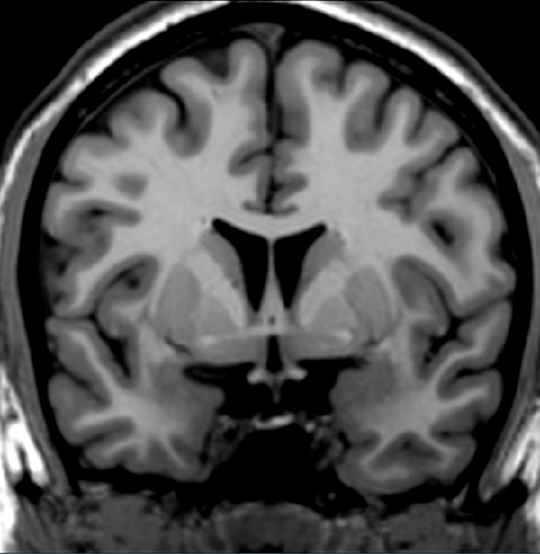

Answer question 4.

Correct! The previous scan was rostral to this scan through the arterior commissure.